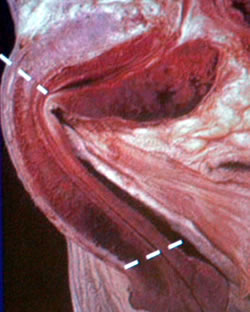

Передняя

уретра

Висячая

Бульбозная